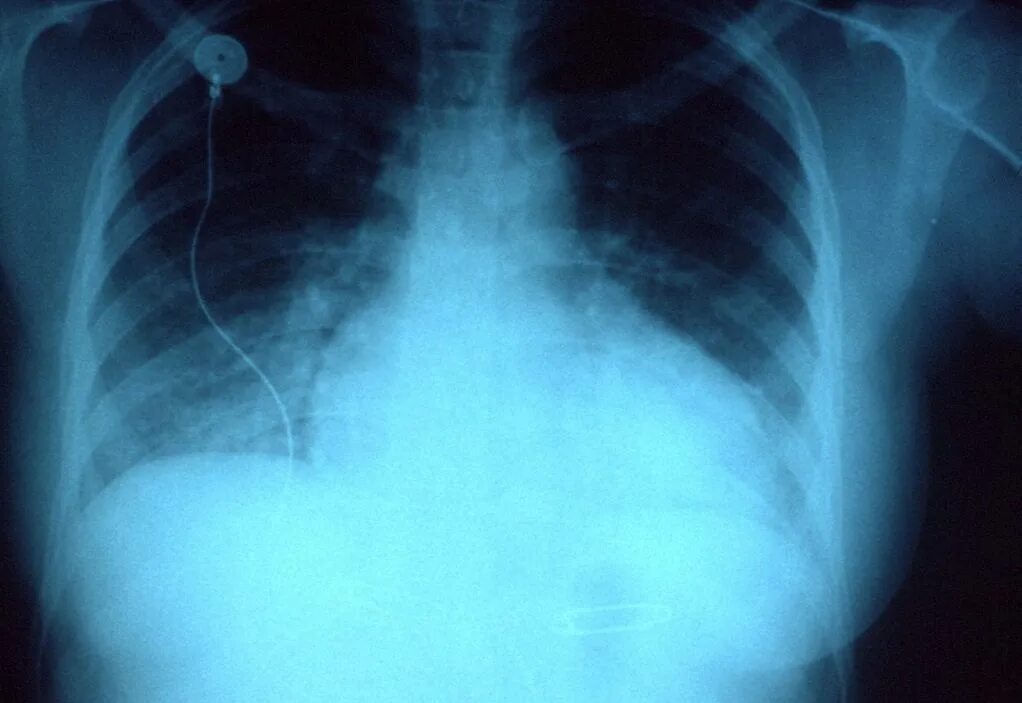

Делала рентген при беременности